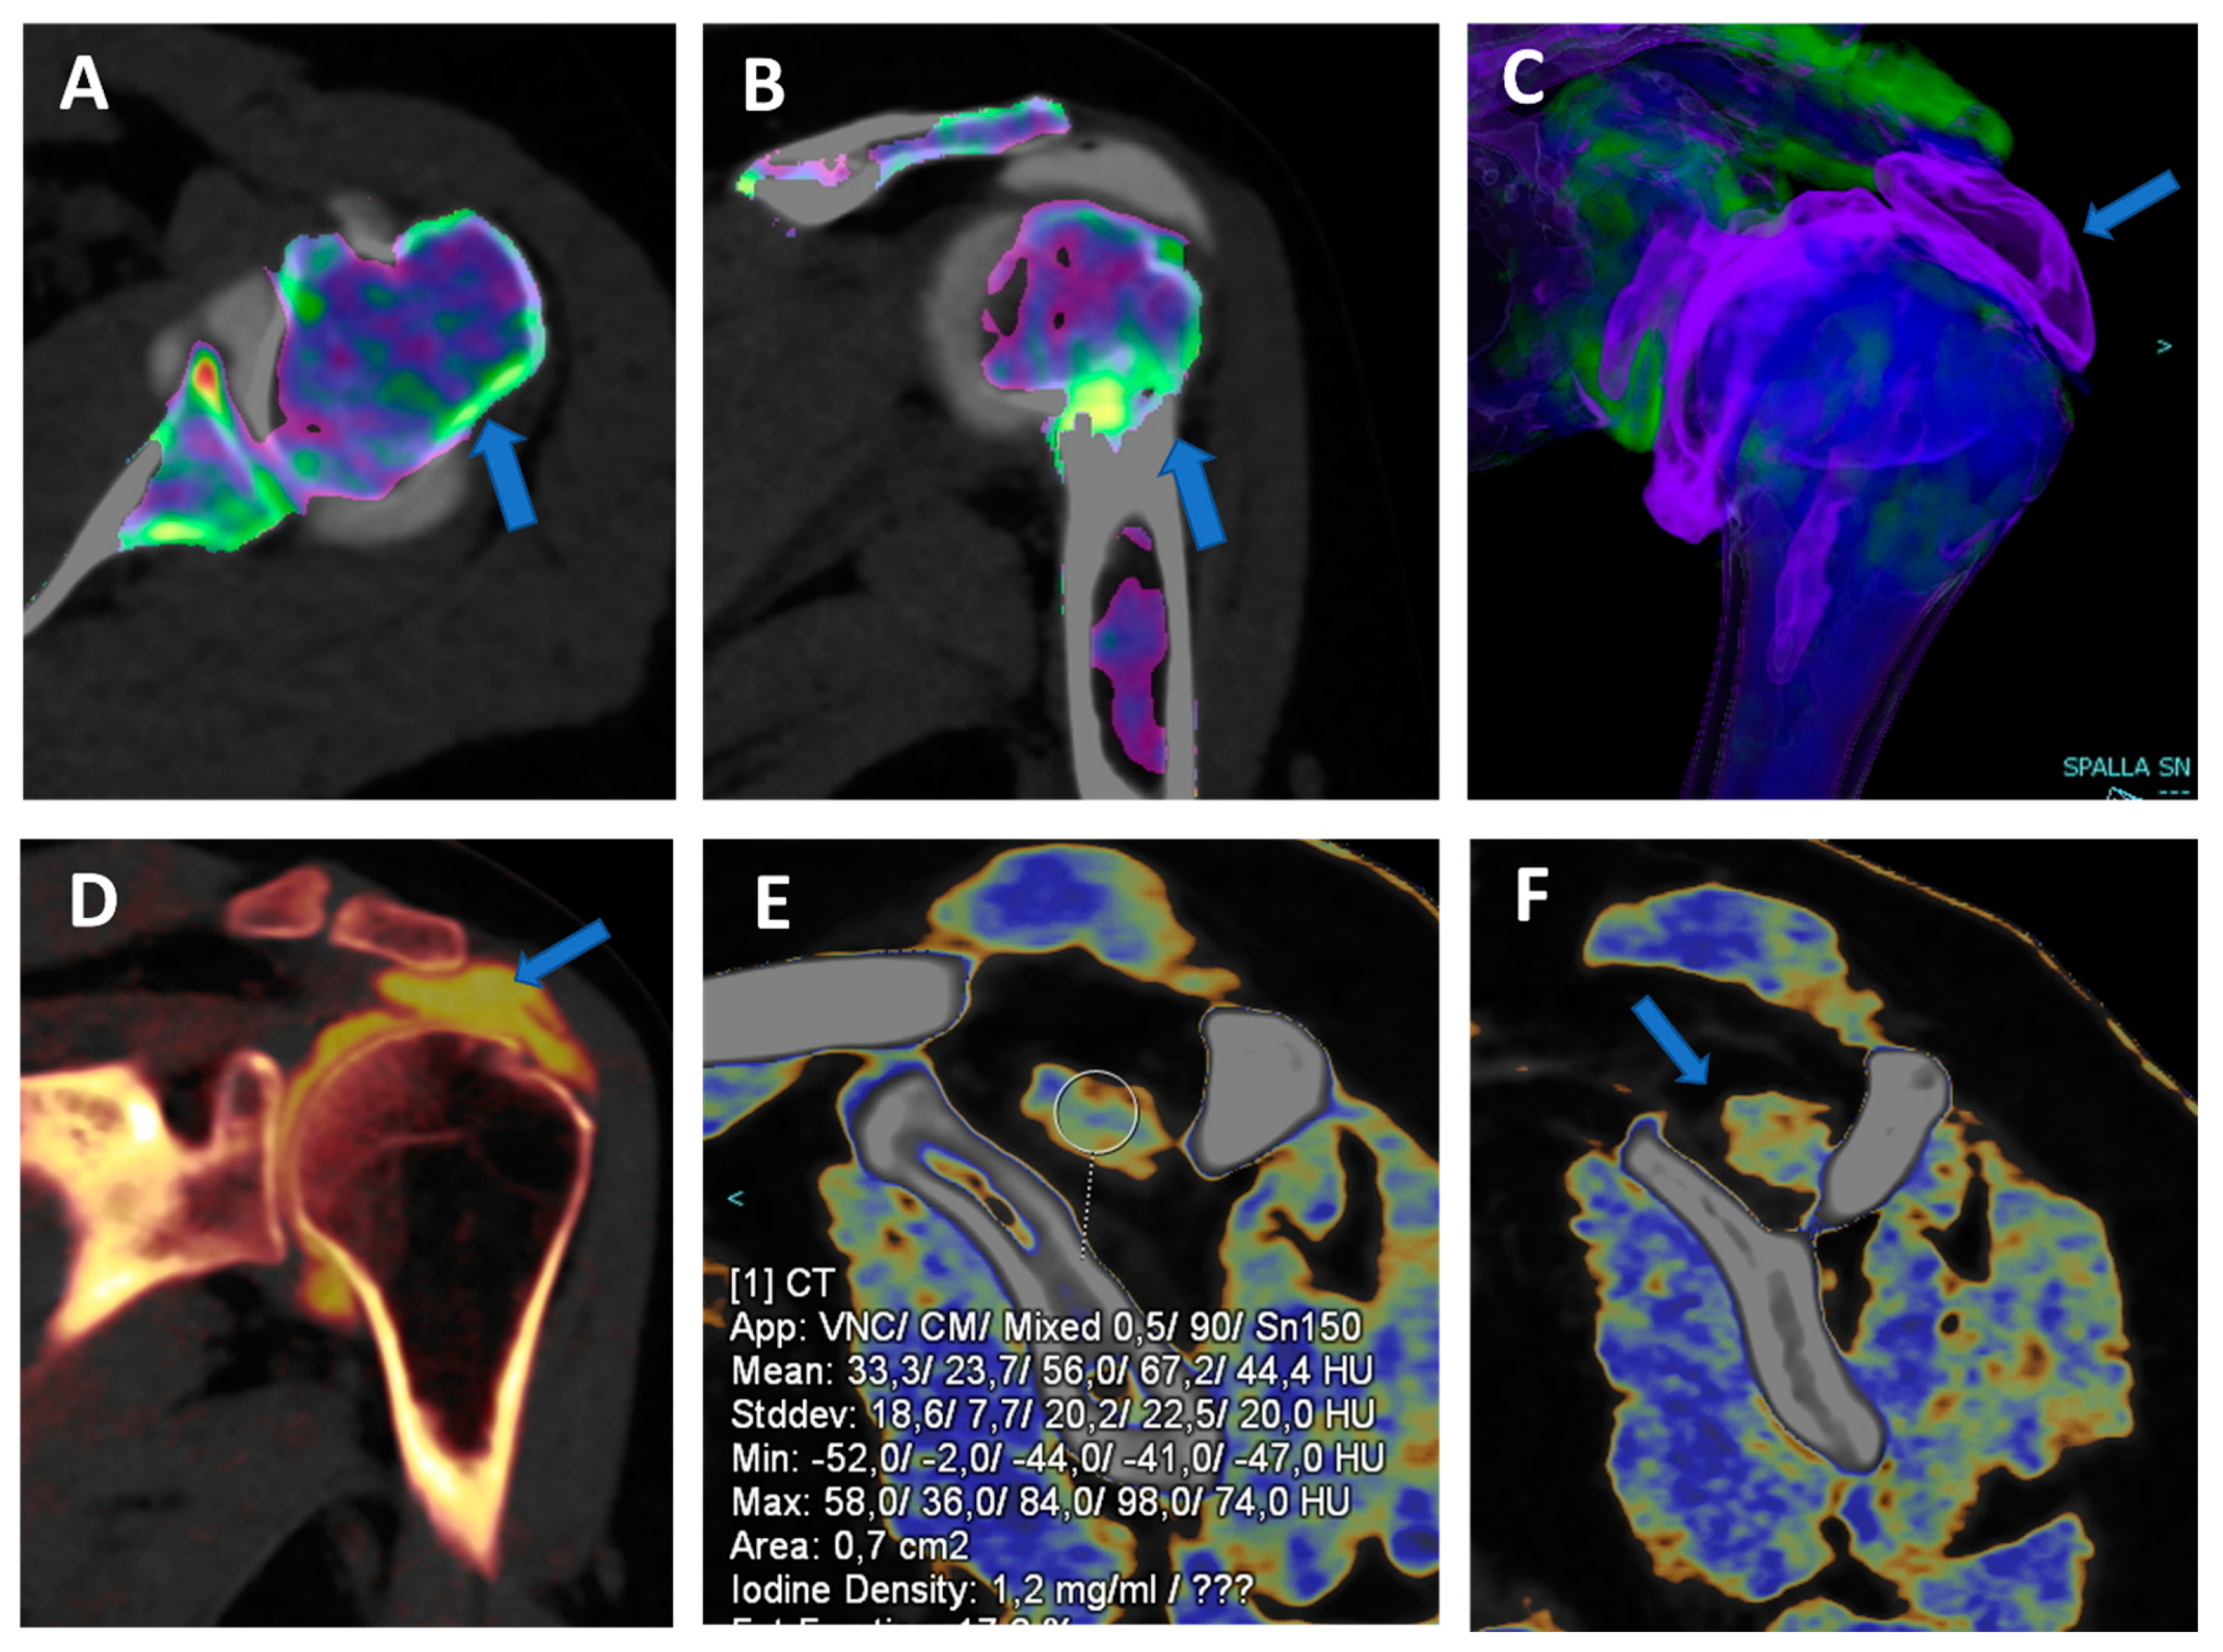

VNC images can generate a “fat map” that could be used to identify and quantify the presence of atrophy of the peri-articular muscle belly (Figure 6) [25]. In the study by Molwitz et al., dual-energy CT material decomposition and virtual non-contrast-enhanced DECT HU values were successfully employed to reliably assess muscle fat [25]. In particular, studying 21 patients and using MRI as the reference for diagnosis, the authors measured HU values on VNC DECT images in 126 regions of interest within the posterior paraspinal muscle, achieving a very good correlation between DECT and MRI (r = 0.91; r = −0.98). For this reason, dual-energy computed tomography could represent an alternative tool for the assessment of muscle quality, an important parameter for the risk of recurrent tendon or ligament tears around joints.

Traumatic anterior shoulder dislocation with rotator cuff complete tear and Hill Sachs lesion. On the 2D 1 mm axial and coronal reconstructed VNCa images (A,B), a subtle depression of the posterior aspect of the humeral head is visible, with mild edema coded in green on the superimposed map (arrow). The 3D VNCa image (C) clearly shows the passage of contrast material in the sub-acromial space (arrow). On the coronal 1 mm reconstructed iodine map image (D), the complete rupture of the rotator cuff is beautifully confirmed (arrow). On the sagittal LNC images (E,F), it is possible to identify (arrow on (F)) and quantify (ROI on (E)) the presence of atrophy of the muscle belly.

For example, DECT virtual non-contrast (VNC) images may be used to avoid the acquisition of non-contrast images, with a subsequent reduction in radiation dose to the patient [19,20]. VNC images are routinely employed for the assessment of abdominal parenchyma [21] and vascular imaging [22]. Moreover, VNC images from dual-energy CT arthrography (DECTA) of the shoulder with iodine removal have been proposed for the assessment of the glenoid morphology and for quantitative measurements of the glenoid area [19]. Similarly, 2D and 3D high-resolution CT bone images can be used for pre-operative planning in cases of femoro-acetabular impingement syndrome [20]. This clinical need for the identification and quantification of both cartilaginous and bone defects is of great importance for the surgeon, especially for those patients with shoulder dislocation. Additionally, 3D reconstruction, allowed by CT, is now often requested by orthopedic surgeons for hip, knee, ankle, and elbow surgery as well, because it is employed for surgical planning. In this scenario, CT could play a key role in representing a “one-stop one-shop” exam, allowing both intra-articular evaluation and 3D assessment of the involved joint.

During post-processing, we achieve three datasets of images (thickness 0.75 mm; increment 0.6 mm): an 80-kVp set, a 150-kVp set, and a blended virtual 120 kVp set of images with a Br 64 kernel—osteo-window filter. Moreover, soft-tissue kernel (Qr32) 80-kVp and 150-kVp sets of images are reconstructed on an off-line workstation (SyngoVia® VB20; Siemens, Erlangen, Germany). A three-material decomposition algorithm is applied, and multiple lookup tables are available. Applications are chosen according to the radiologist’s preference. VMI is employed to achieve a VNC dataset for bone measurements or to reduce artifacts in the case of metallic components. Iodine maps are used to enhance the visualization of subtle labral or tendon tears. Additionally, in the case of small articulations such as the wrist or elbow, 0.3 mm reconstructions are obtained to improve the visualization of tiny articular anatomic structures and subtle cartilage lesions. Finally, BME maps are obtained in cases of trauma to rule out or confirm the presence of BME around the imaged joint.